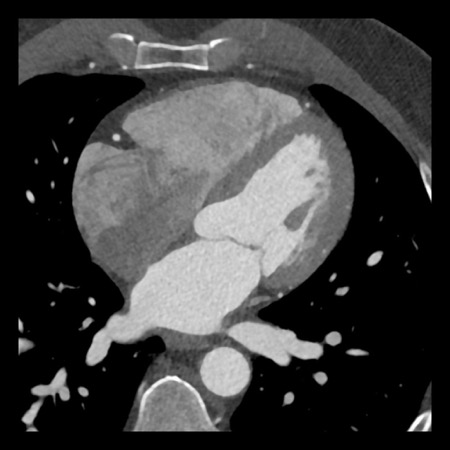

case 4 – CAD-RADS 3/P1/I+ thrombus left ventricle

First, scroll through the CTA images.

How would you describe the findings on the coronary CTA?

The findings are:

- Moderate (50-69%)

stenosis in the proximal LAD caused by a non-calcified plaque. - Variant of

sinoatrial (SA) nodal artery. The artery usually arises from the RCA as a second

branch after the conus artery, however in this case it arises from the LCX,

courses behind the aorta, anastomosing with the right atrium and with a small

branch supplies the SA-node of the heart. - Thrombus in the

apex of the left ventricle. - CTP was performed

in this patient. CTP showed a perfusion defect at stress imaging in the

territory of the LAD (I+), at rest no perfusion defect was visible.

This patient classifies as CAD-RADS 3/P1/I+, which means

this patient requires further investigation.